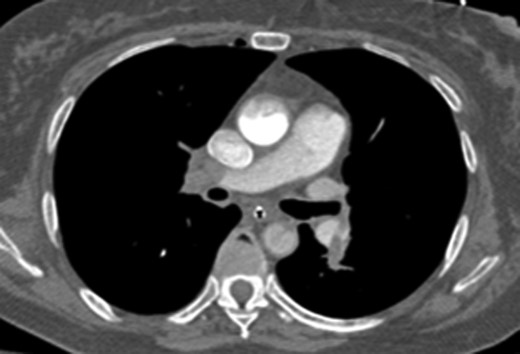

A 61-year-old female initially presented to the emergency department with shortness of breath and back pain. The patient had recently traveled to Haiti and made several trips to Denver by car. She was initially alert and oriented but sustained a cardiac arrest shortly after arrival and underwent CPR for pulseless electrical activity (PEA). Approximately 5 min into resuscitative efforts, a LUCAS 2.0 (Physio-Control Inc., Lund, Sweden) device was placed for continued chest compressions for 30 min. Bedside echocardiogram showed a dilated RV with a suspected massive PE and the ECMO team was activated. The patient was intubated and VA-ECMO access was obtained through the left femoral artery and right common femoral vein under ultrasound guidance with 17 Fr arterial and 25 Fr venous cannulas (Fig. 1). After a total of 35 min of CPR, the patient had spontaneous return of circulation.

Abdominal x-ray of VA-ECMO cannulation within the IVC and left iliac artery.